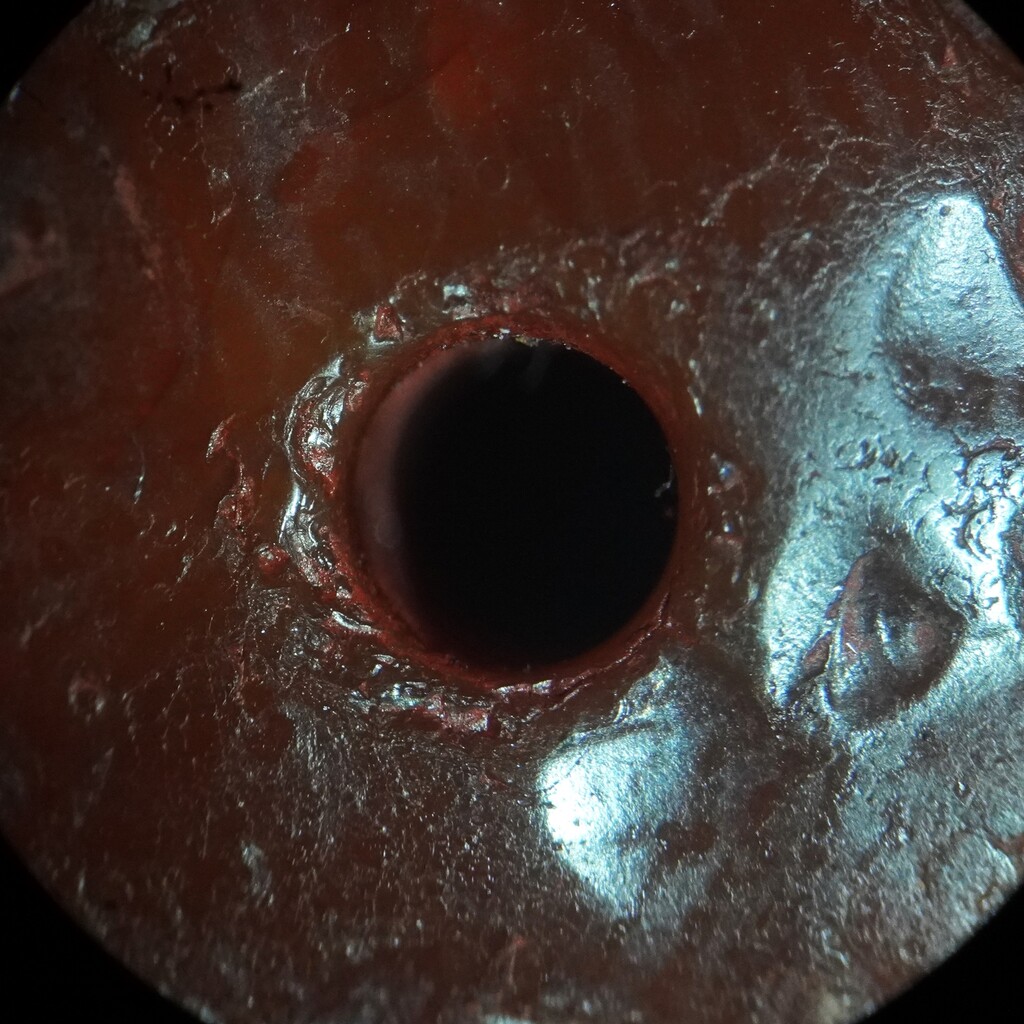

甸的神玉髓古珠.

出土文物.地埋古珠.

不的八角型珠.

有.斑沁..洞.瑙虹化...等地埋特徵

有3手指和神生物部.特殊造型的古珠.